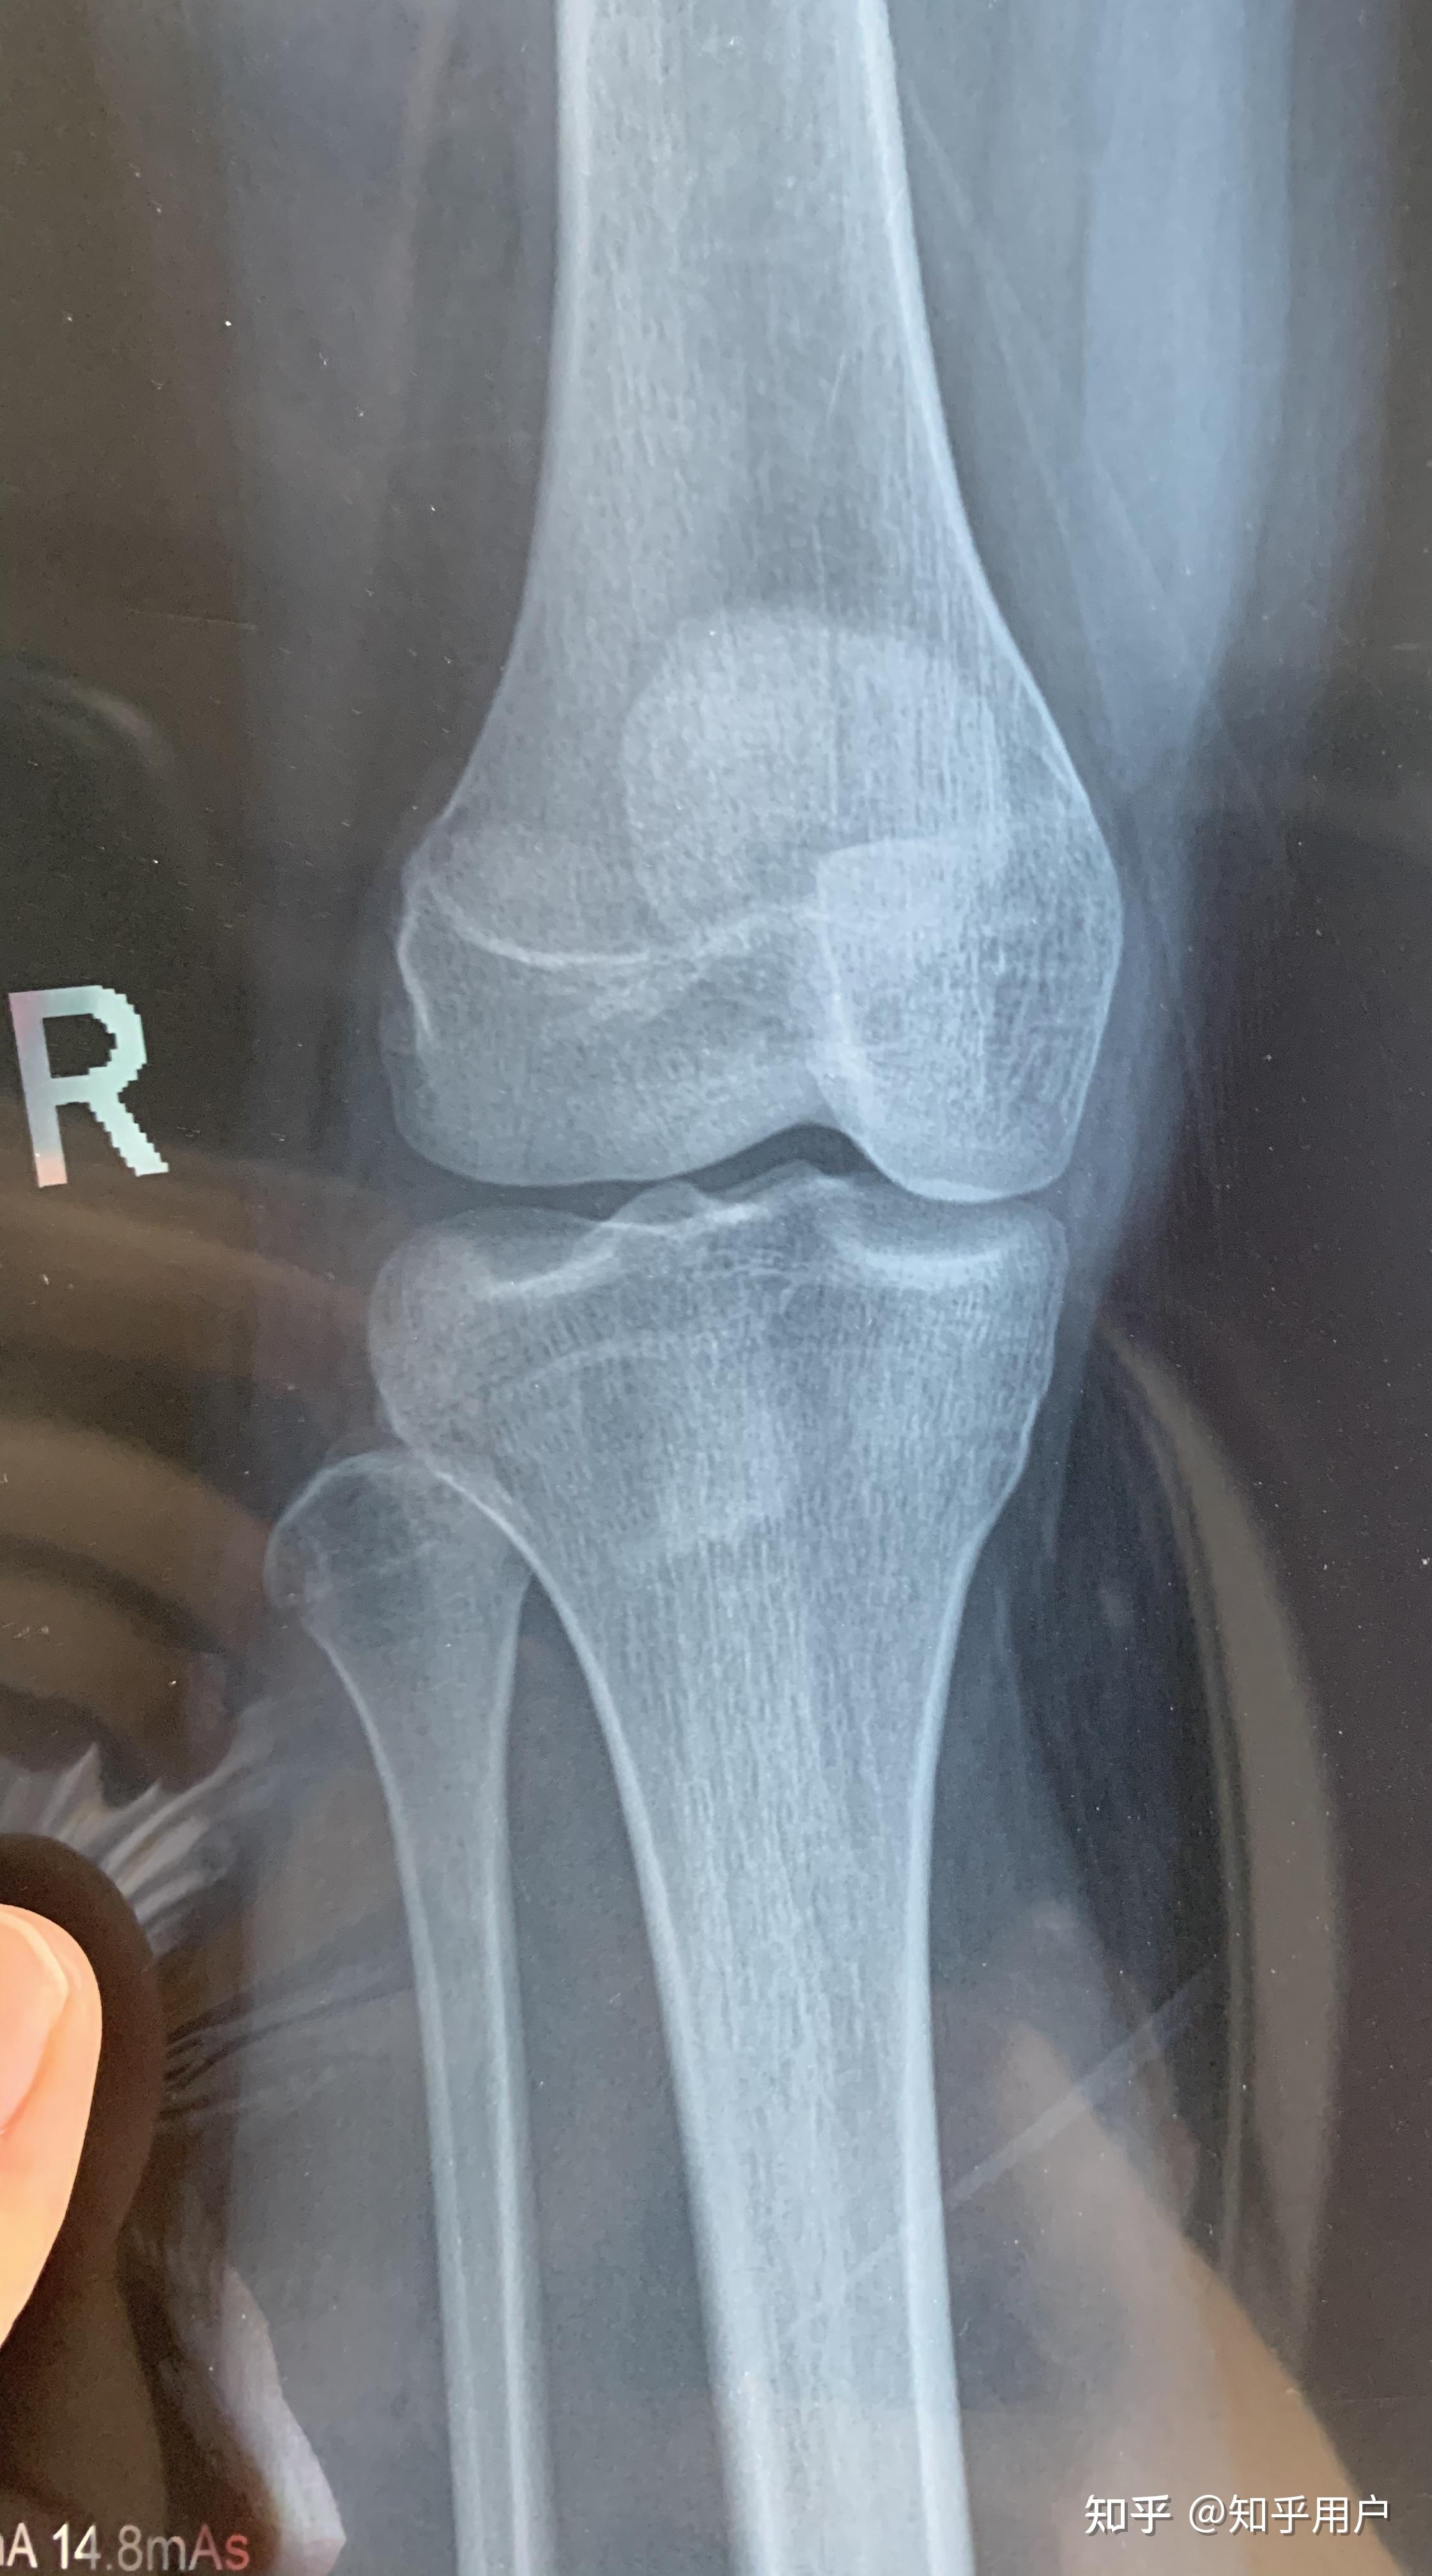

请问我的骨骼线有没有完全闭合,还有长高的希望吗?? - 知乎

图片尺寸1536x2048